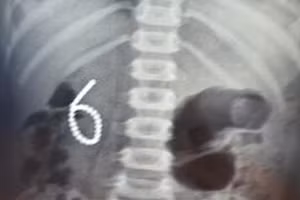

Lấy 28 viên bi nam châm trong bụng bệnh nhi 4 tuổi 12/07/2022 11:48 GD&TĐ - Vừa qua, Khoa Ngoại Tổng H ợp – Bệnh viện Nhi Thanh Hóa vừa phẫu thuật thành công ca bệnh dị vật đường tiêu hóa cháu Đ.N.D.A (04 tuổi), ở huyện Nông Cống, tỉnh Thanh Hóa.